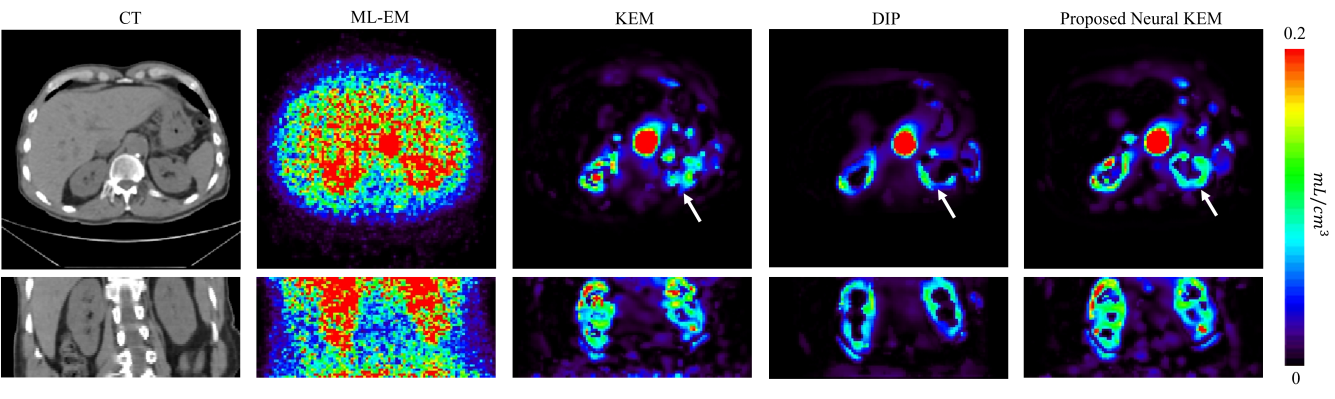

Fig. 11 shows the comparison of different reconstructions for a late 5-minute frame () and two early 2-s frames (, ). Each reconstruction is shown in the transverse and coronal views.

For the 5-minute frame which has a relatively high count level, the ML-EM reconstruction had good contrast in the tumor region though still contained high noise in the normal liver parenchyma. The DIP by OT caused over-smoothness and demonstrated a distortion in the tumor as pointed by the arrow in Fig. 11(a). With a preserved tumor shape similar to that of the ML-EM, both the regular KEM and neural KEM suppressed noise well and provided similar results in this high-count reconstruction, though the latter may have a slightly higher risk of oversmoothing small targets or sharp edges for higher count data due to the additional regularization from the use of deep coefficient prior.

For the 2-s frames, the ML-EM reconstructions were extremely noisy. The DIP by OT significantly reduced noise but tended to over-smooth the images. In Fig. 11(b), KEM resulted in a discontinuous aorta while the proposed neural KEM showed a more natural shape. In Fig. 11(c), the neural KEM also showed a more continuous renal cortex, which may benefit parametric imaging as will be presented in the next subsection. To sum up, the proposed neural KEM not only suppressed the noise in the background regions but also preserved structural contrast and details, though it cannot exclude a potential risk of over-regularization similar to any other methods that includes a regularization. Here the neural KEM and DIP by OT showed different anatomical structures in these two low-count frames. While there is no ground truth and the ML-EM was too noisy to provide a reference, the result from the high-count frame shown in Fig. 11(a) may imply the result by the neural KEM is more likely to be close to the truth of the low-count frames.